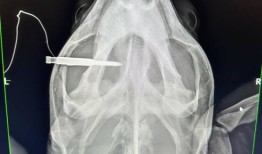

上周,佛罗里达群岛的兽医们发现了一只头部被长矛刺穿的红海龟,他们尽了一切努力来拯救它。但到了周六,他...